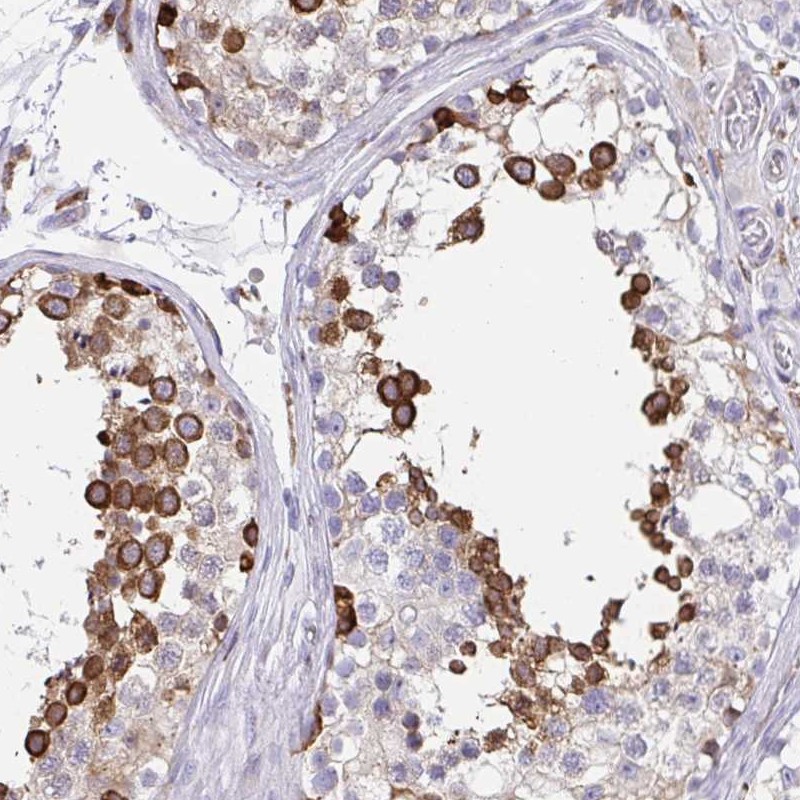

Immunohistochemical staining of human testis shows strong cytoplasmic positivity in subset of cells in seminiferus ducts.